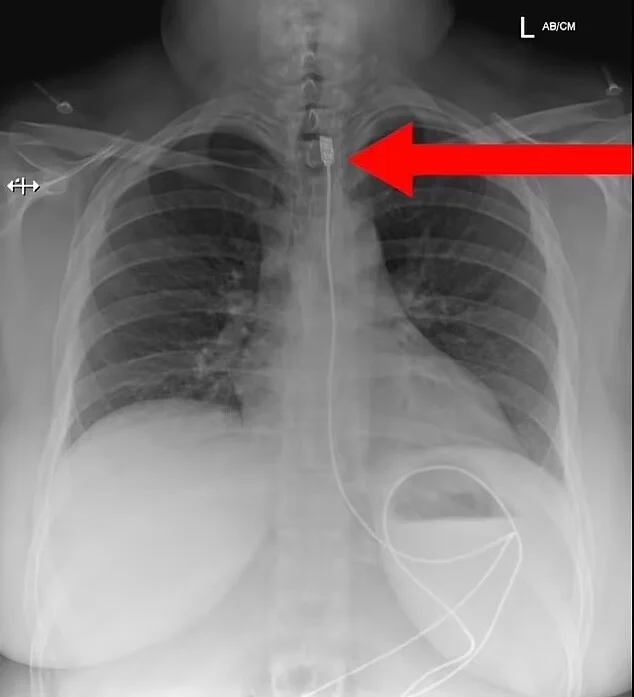

Γυναίκα που πάσχει από μια σπάνια διατροφική διαταραχή χρειάστηκε να υποβληθεί σε επείγουσα χειρουργική επέμβαση αφού προσπάθησε να καταπιεί ένα καλώδιο φορτιστή iPhone μήκους σχεδόν ενός μέτρου.

Η γυναίκα από την Πολωνία φέρεται να πάσχει από Pica, διαταραχή που συνδέεται με την κατανάλωση μη φαγώσιμων ουσιών.

Μεταφέρθηκε εσπευσμένα στο χειρουργείο αφού το καλώδιο σφηνώθηκε στον οισοφάγο της.

Καλώντας τις υπηρεσίες έκτακτης ανάγκης αφού άρχισε να ασφυκτιά, η γυναίκα φέρεται να έλαβε επείγουσα θεραπεία για την αφαίρεση του καλωδίου, σύμφωνα με την Daily Mail.

Δημοσιεύοντας μια ακτινογραφία στο Facebook, μια ομάδα με την ονομασία «Ready to Rescue» που κάνει μαθήματα Πρώτων Βοηθειών στην πολωνική πόλη Wroclaw ανέφερε:

Η φωτογραφία δημοσιεύτηκε αρχικά στη σελίδα στα social media μιας ομάδας που αυτοαποκαλείται Savage Paramedics, η οποία περιγράφει τον εαυτό της ως «μια κοινότητα για επαγγελματίες υγείας που συναντιούνται για χιούμορ, διασκέδαση και εκπαίδευση», και πρωτοεμφανίστηκε το Σάββατο.

Συνοδευόταν από μια άλλη φωτογραφία που έδειχνε σε κοντινό πλάνο τον φορτιστή του τηλεφώνου που είχε σφηνωθεί μέσα στο λαιμό της γυναίκας.

«Το καλώδιο αφαιρέθηκε με επιτυχία στο νοσοκομείο και η γυναίκα ανάρρωσε πλήρως. Ωστόσο δεν είπε σε κανέναν τον λόγο για τον οποίο κατάπιε αρχικά το καλώδιο φόρτισης. Καμία ιδέα;», ανέφερε η ομάδα.